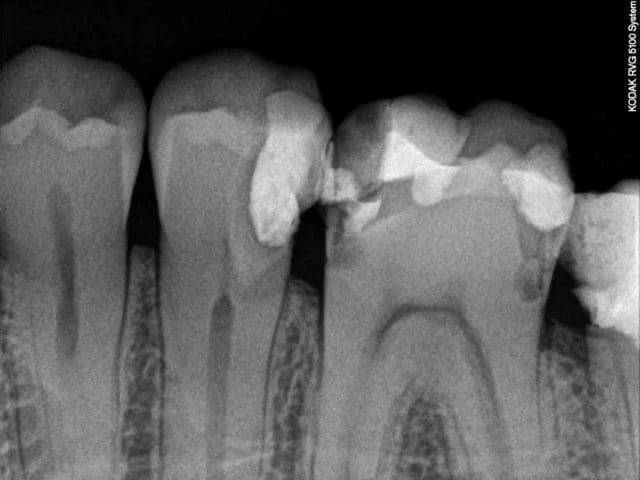

Patient vus à un mois d'intervalle pour des douleurs. Pas de devis miroboland, des CCM à 500 euros qui feront plaisir à santéclair ou à notre ministre de la mauvaise santé, secteur campagne.

Vus la premiere fois pour un debut d'infection sous 47 un samedi à la fermeture, demontage du screw post, allésage laissée ouverte avec une prescription puis retours chez mon confrére.

Puis un mois plus tard retour un samedi pour des douleurs suite à l'obturation de 46, endo metasonne, cône de 2%, canal ML et DL non preparés, démontage du cône DV avec le coton laissé dans la chambre.

Il n'ai pas besoin de faire des devis delirant ou de partiquer des tarifs de prothése excessifs pour mal faire notre travail.

Il a l'air doué ce dentiste ... il aurait pu faire la couronne sans faire l'endo sur la 6 et on fait semblant de pas avoir vu la fracture d'instrument sur la 7

Les patients sont mieux armés pour discuter de la réalité d'un devis gonflé, que sur la qualité des soins de bases. La 8 ne fait pas mal et si le ML ne saignait pas encore dans la dent "obturée", le traitement serait allé à son terme avec des CCM à 500 euro réalisées sur çà.